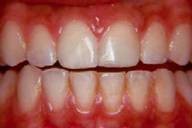

Case 2

missing

Before

After

As you can see, tooth-coloured fillings substantially improve the beauty of your teeth.